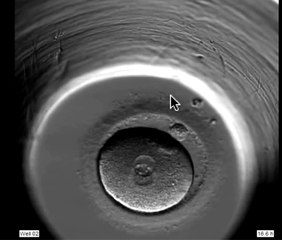

Artificial Intelligence to Help Fertility Doctors Choose the Best Embryos for IVF

IVF is responsible for between 1 to 2 of all births in the US. The process is expensive, averaging over 12,000 persession, and most women require more than one attempt. Veuer’s Maria Mercedes Galuppo has the story.